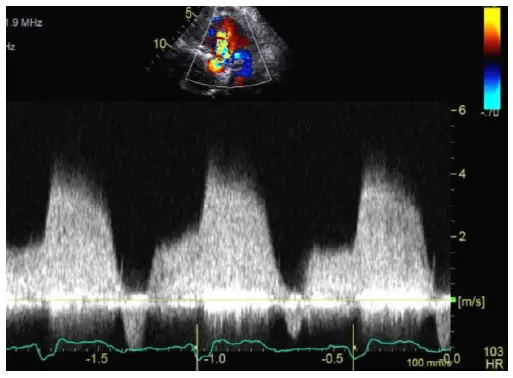

Pressure Half Time (PHT)

Mitral Valve Area (MVA) from PHT